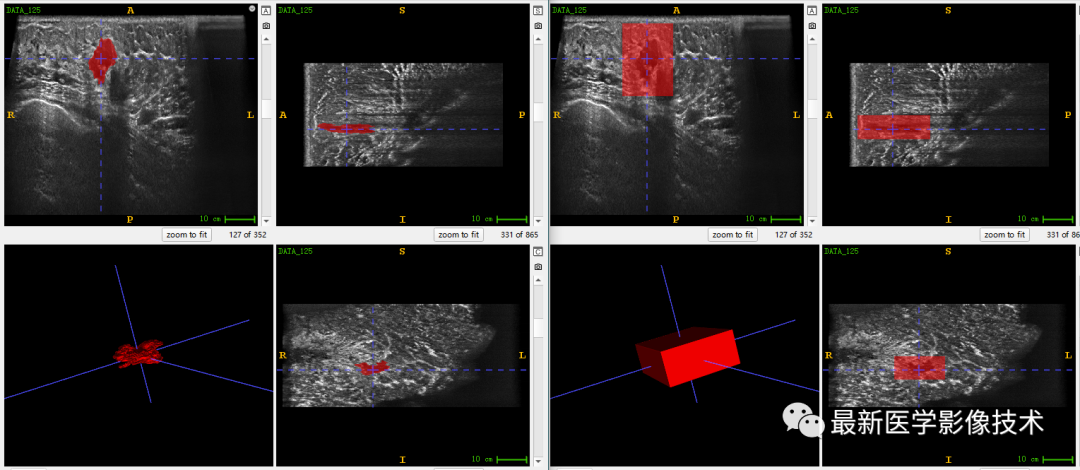

乳腺肿瘤分割采用两阶段分割网络,第一个网络进行粗分割定位肿瘤位置,第二个网络进行精分割得到肿瘤精确轮廓,然后在根据精分割mask和对应ROI图像进行良恶性分类。具体实现可以参考这篇文章TDSC-ABUS2023——2023 年自动化 3D 乳腺超声 (ABUS) 的肿瘤检测、分割和分类挑战.

验证集分割和检测部分结果如下所示。